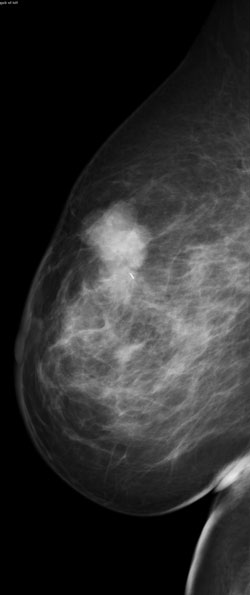

superimposed tissue

A mammogram (above) showing possible asymmetry, with tomosynthesis images (right) showing superimposed tissue.

digital mammogram digital tomosynthesis

Invasive Ductal Carcinoma on digital mammogram (above left) and digital tomosynthesis (above right). Digital tomosynthesis shows clear presence of a spiculated mass.